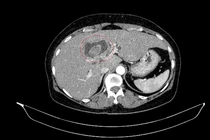

Việc phát hiện đồng thời hai ung thư nguyên phát trong hệ tiêu hóa là rất hiếm. Trường hợp này cho thấy vai trò quan trọng của thăm khám toàn diện.